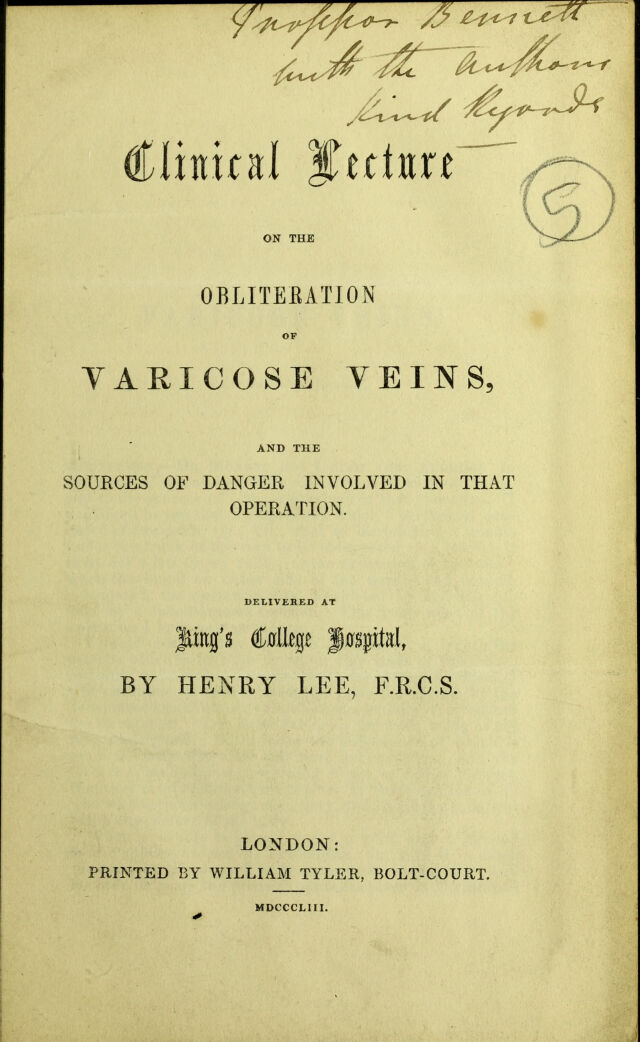

Clinical lecture on the obliteration of varicose veins, and the sources of danger involved in that operation : delivered at King's College Hospital / by Henry Lee.

- Lee, Henry, F.R.C.S.

- 1853

Credit: Clinical lecture on the obliteration of varicose veins, and the sources of danger involved in that operation : delivered at King's College Hospital / by Henry Lee. Source: Wellcome Collection.